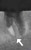

Quick view devemed GmbH Devemed Endodontic Instrument Retrieving Forceps MSRP: $134.95 Was: Now: $100.00